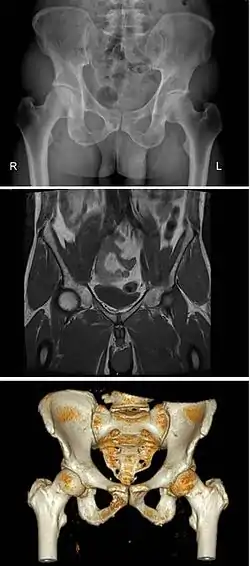

Pelvic bone

2–4. Hip bone (os coxae)

1. Sacrum (os sacrum), 2. Ilium (os ilium), 3. Ischium (os ischii)

4. Pubic bone (os pubis) (4a. corpus, 4b. ramus superior, 4c. ramus inferior, 4d. tuberculum pubicum)

5. Pubic symphysis, 6. Acetabulum (of the hip joint), 7. Obturator foramen, 8. Coccyx/tailbone (os coccygis)

Dotted. Linea terminalis of the pelvic brim.

The pelvic skeleton is formed posteriorly (in the area of the back), by the sacrum and the coccyx and laterally and anteriorly (forward and to the sides), by a pair of hip bones. Each hip bone consists of 3 sections, ilium, ischium, and pubis. During childhood, these sections are separate bones, joined by the triradiate cartilage. During puberty, they fuse together to form a single bone.